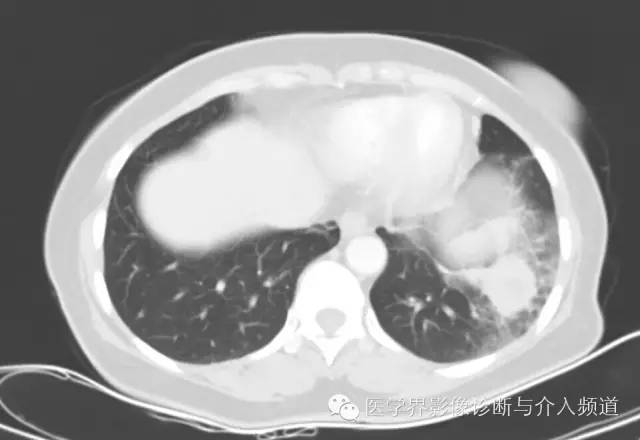

左肺下叶可见软组织密度肿块影,形态不规则,边界不光整,与胸膜粘连不清,周围肺组织呈磨玻璃密度改变,病变内部不均匀强化,低密度区不强化。

硬化性血管瘤

其他征象:钙化、囊变(与出血有关)、周围晕征(非特征性)、周围肺组织肺气肿、增强扫描明显均匀强化(与病变内血管瘤区、乳头区、硬化区、实变区有关)、贴边血管征(肿瘤推挤周围血管,较具特征性)、纵膈及肺门淋巴结(罕见,但有报道)。